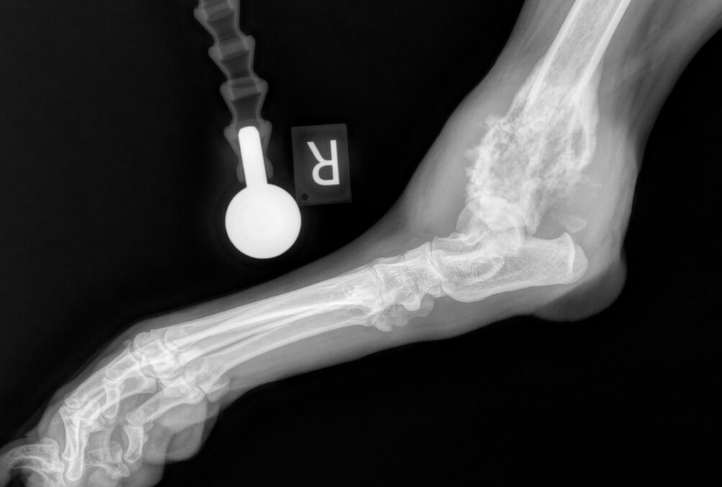

Mediolateral radiograph of the right tarsus illustrating osteosarcoma (OSA) of the distal tibia taken from https://www.fitzpatrickreferrals.co.uk/orthopaedics/canine-osteosarcoma/